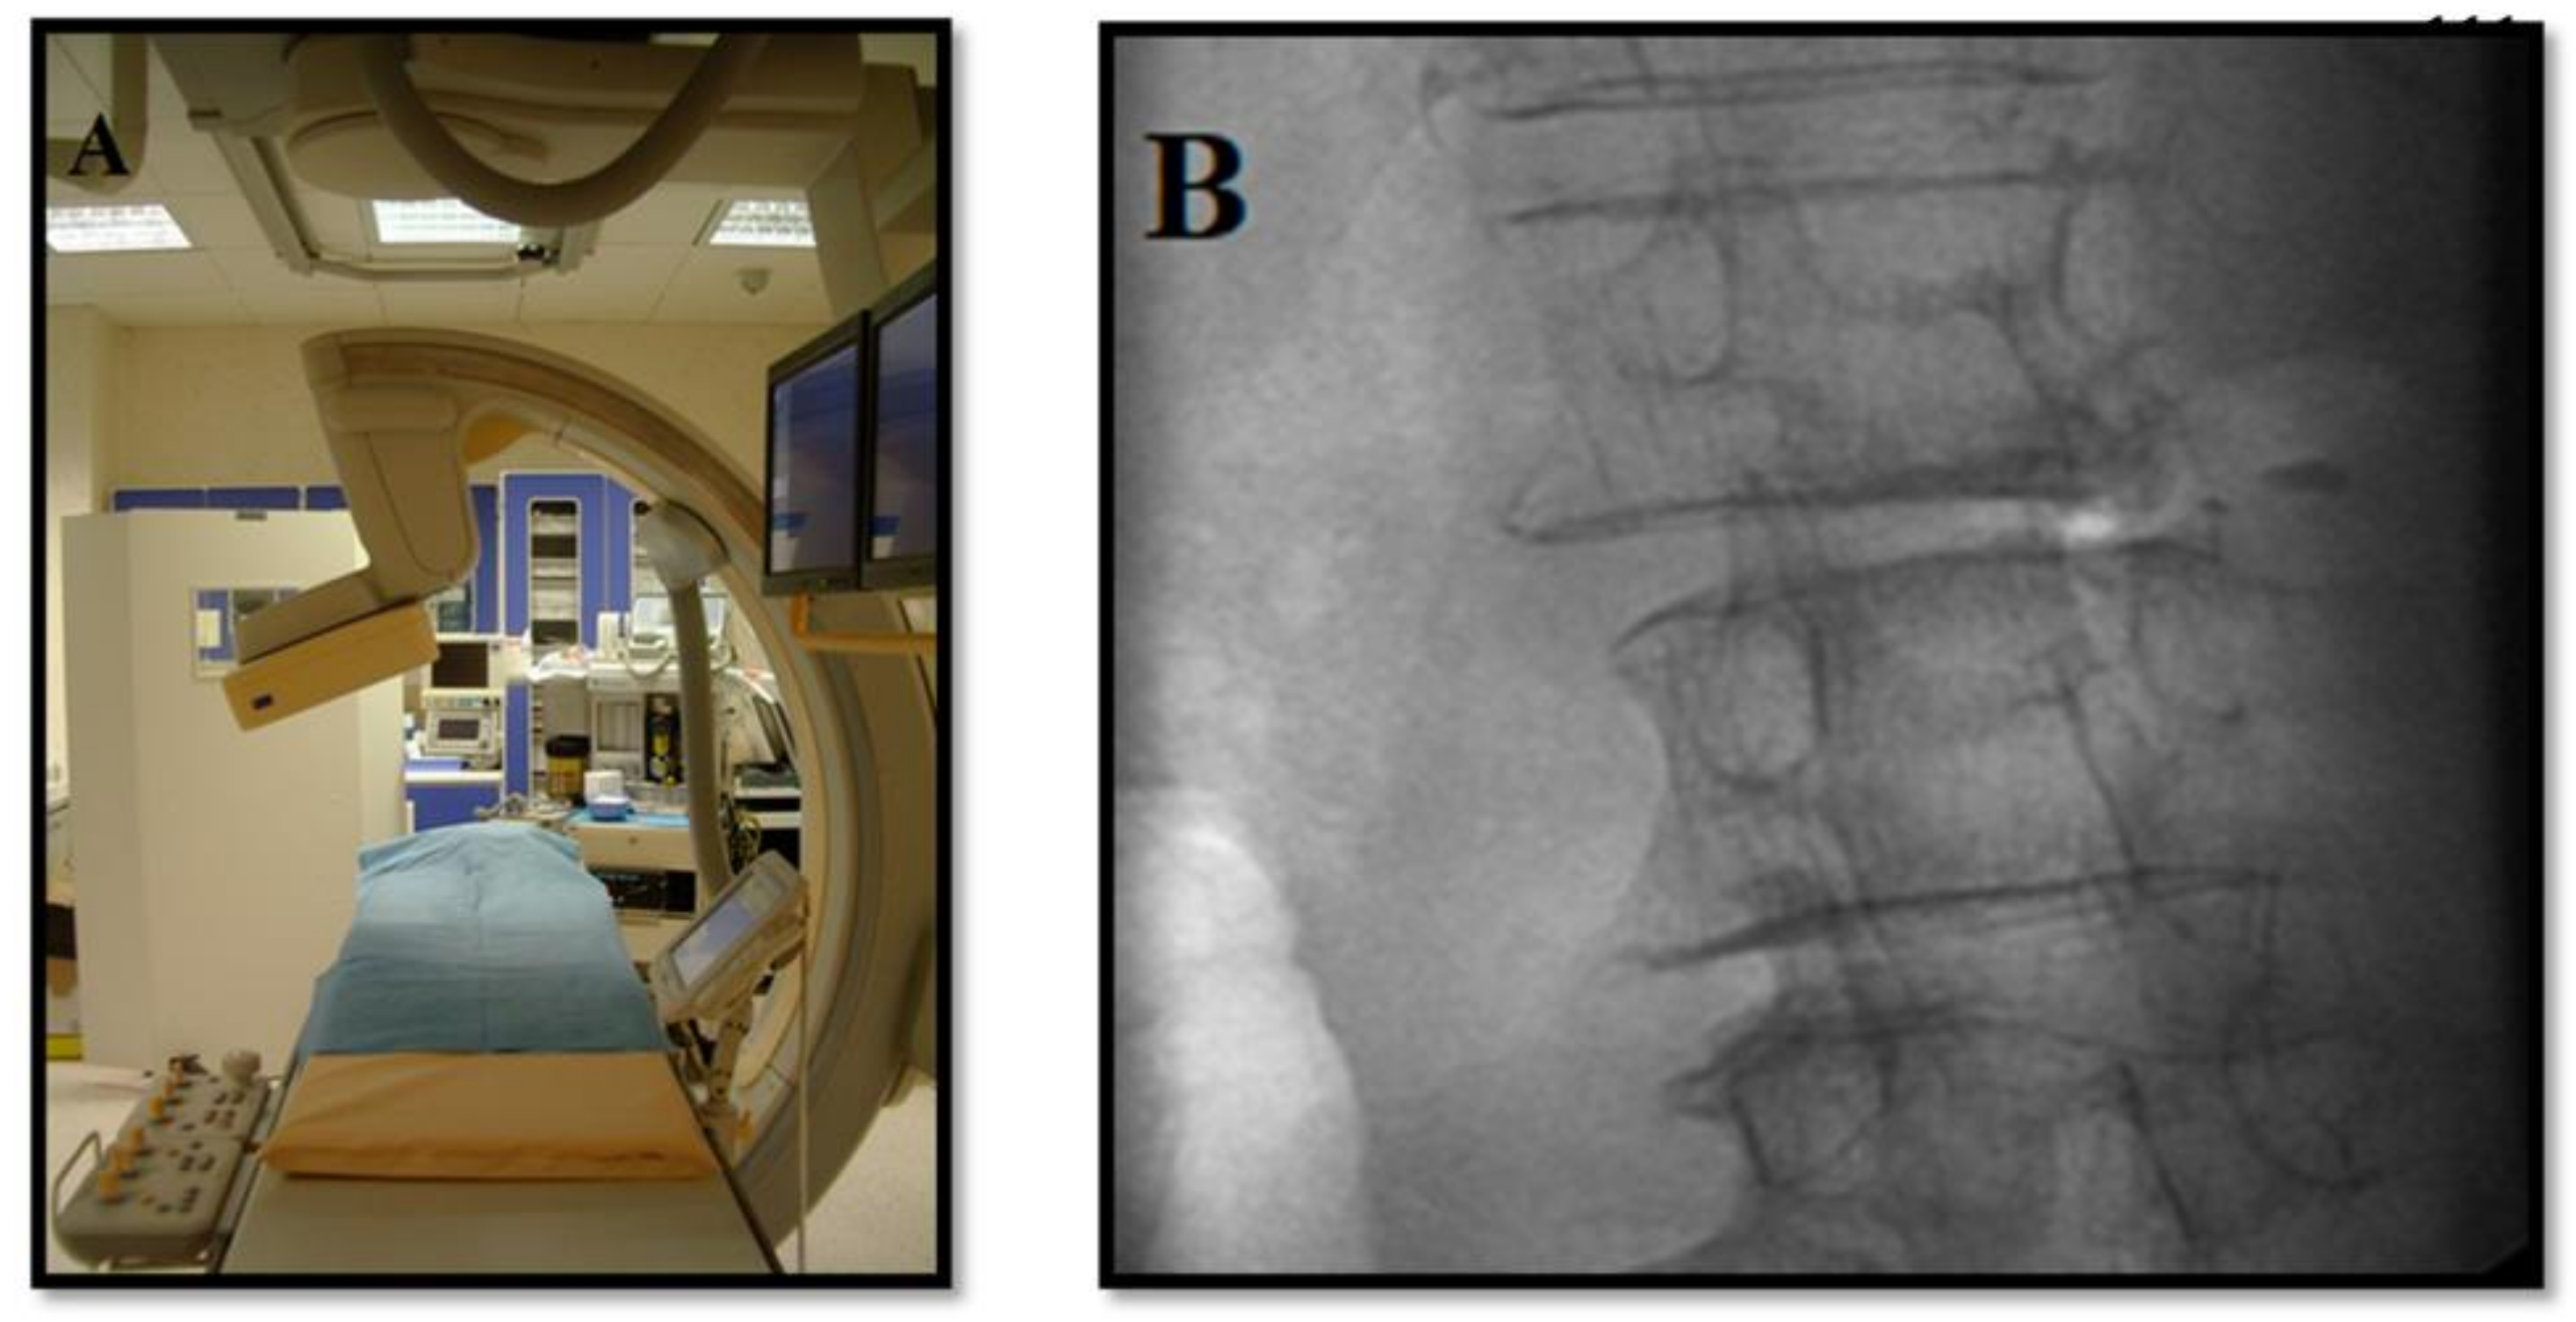

2. Techniques

Mechanical, Thermal, or Chemical Decompression Techniques